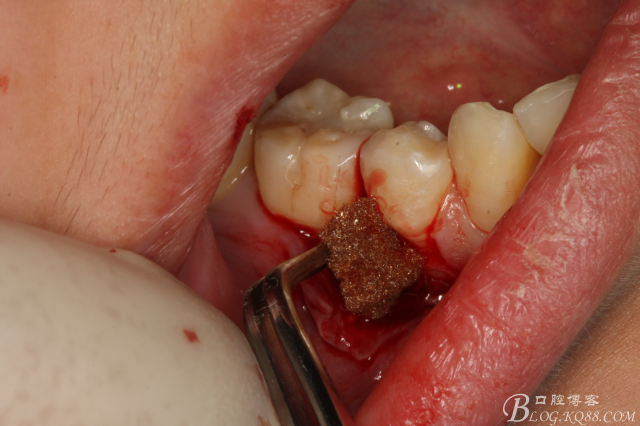

圖14.緩慢在余留牙根周圍用挺,挺松45余留牙根

圖15.挺松的45牙根,牙根已脫位至創(chuàng)口邊緣。

圖16.取出45牙根,牙槽窩完整、不變形。

圖17.清理牙槽窩,切口止于膜齦聯(lián)合處,這樣術(shù)后不腫脹。

圖18.放膠質(zhì)銀